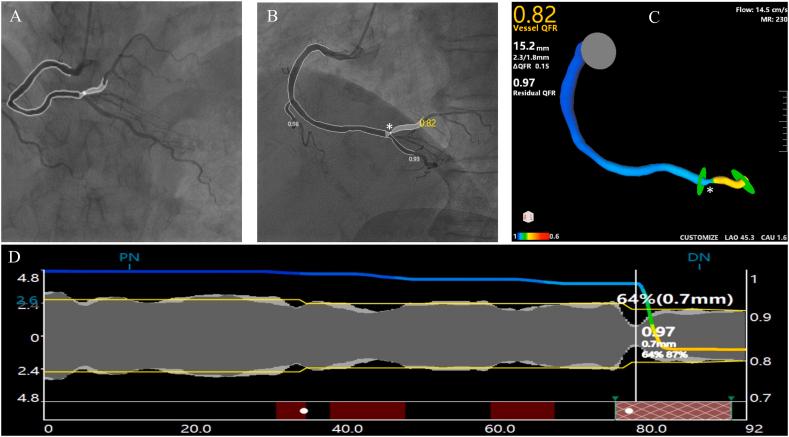

2-Year Outcomes of Angiographic Quantitative Flow Ratio-Guided Coronary Interventions.

J Am Coll Cardiol. 2022 Nov 29;80(22):2089-2101. doi: 10.1016/j.jacc.2022.09.007. Epub 2022 Sep 19.

Angiographic quantitative flow ratio-guided coronary intervention (FAVOR III China): a multicentre, randomised, sham-controlled trial.

Lancet. 2021 Dec 11;398(10317):2149-2159. doi: 10.1016/S0140-6736(21)02248-0. Epub 2021 Nov 4.